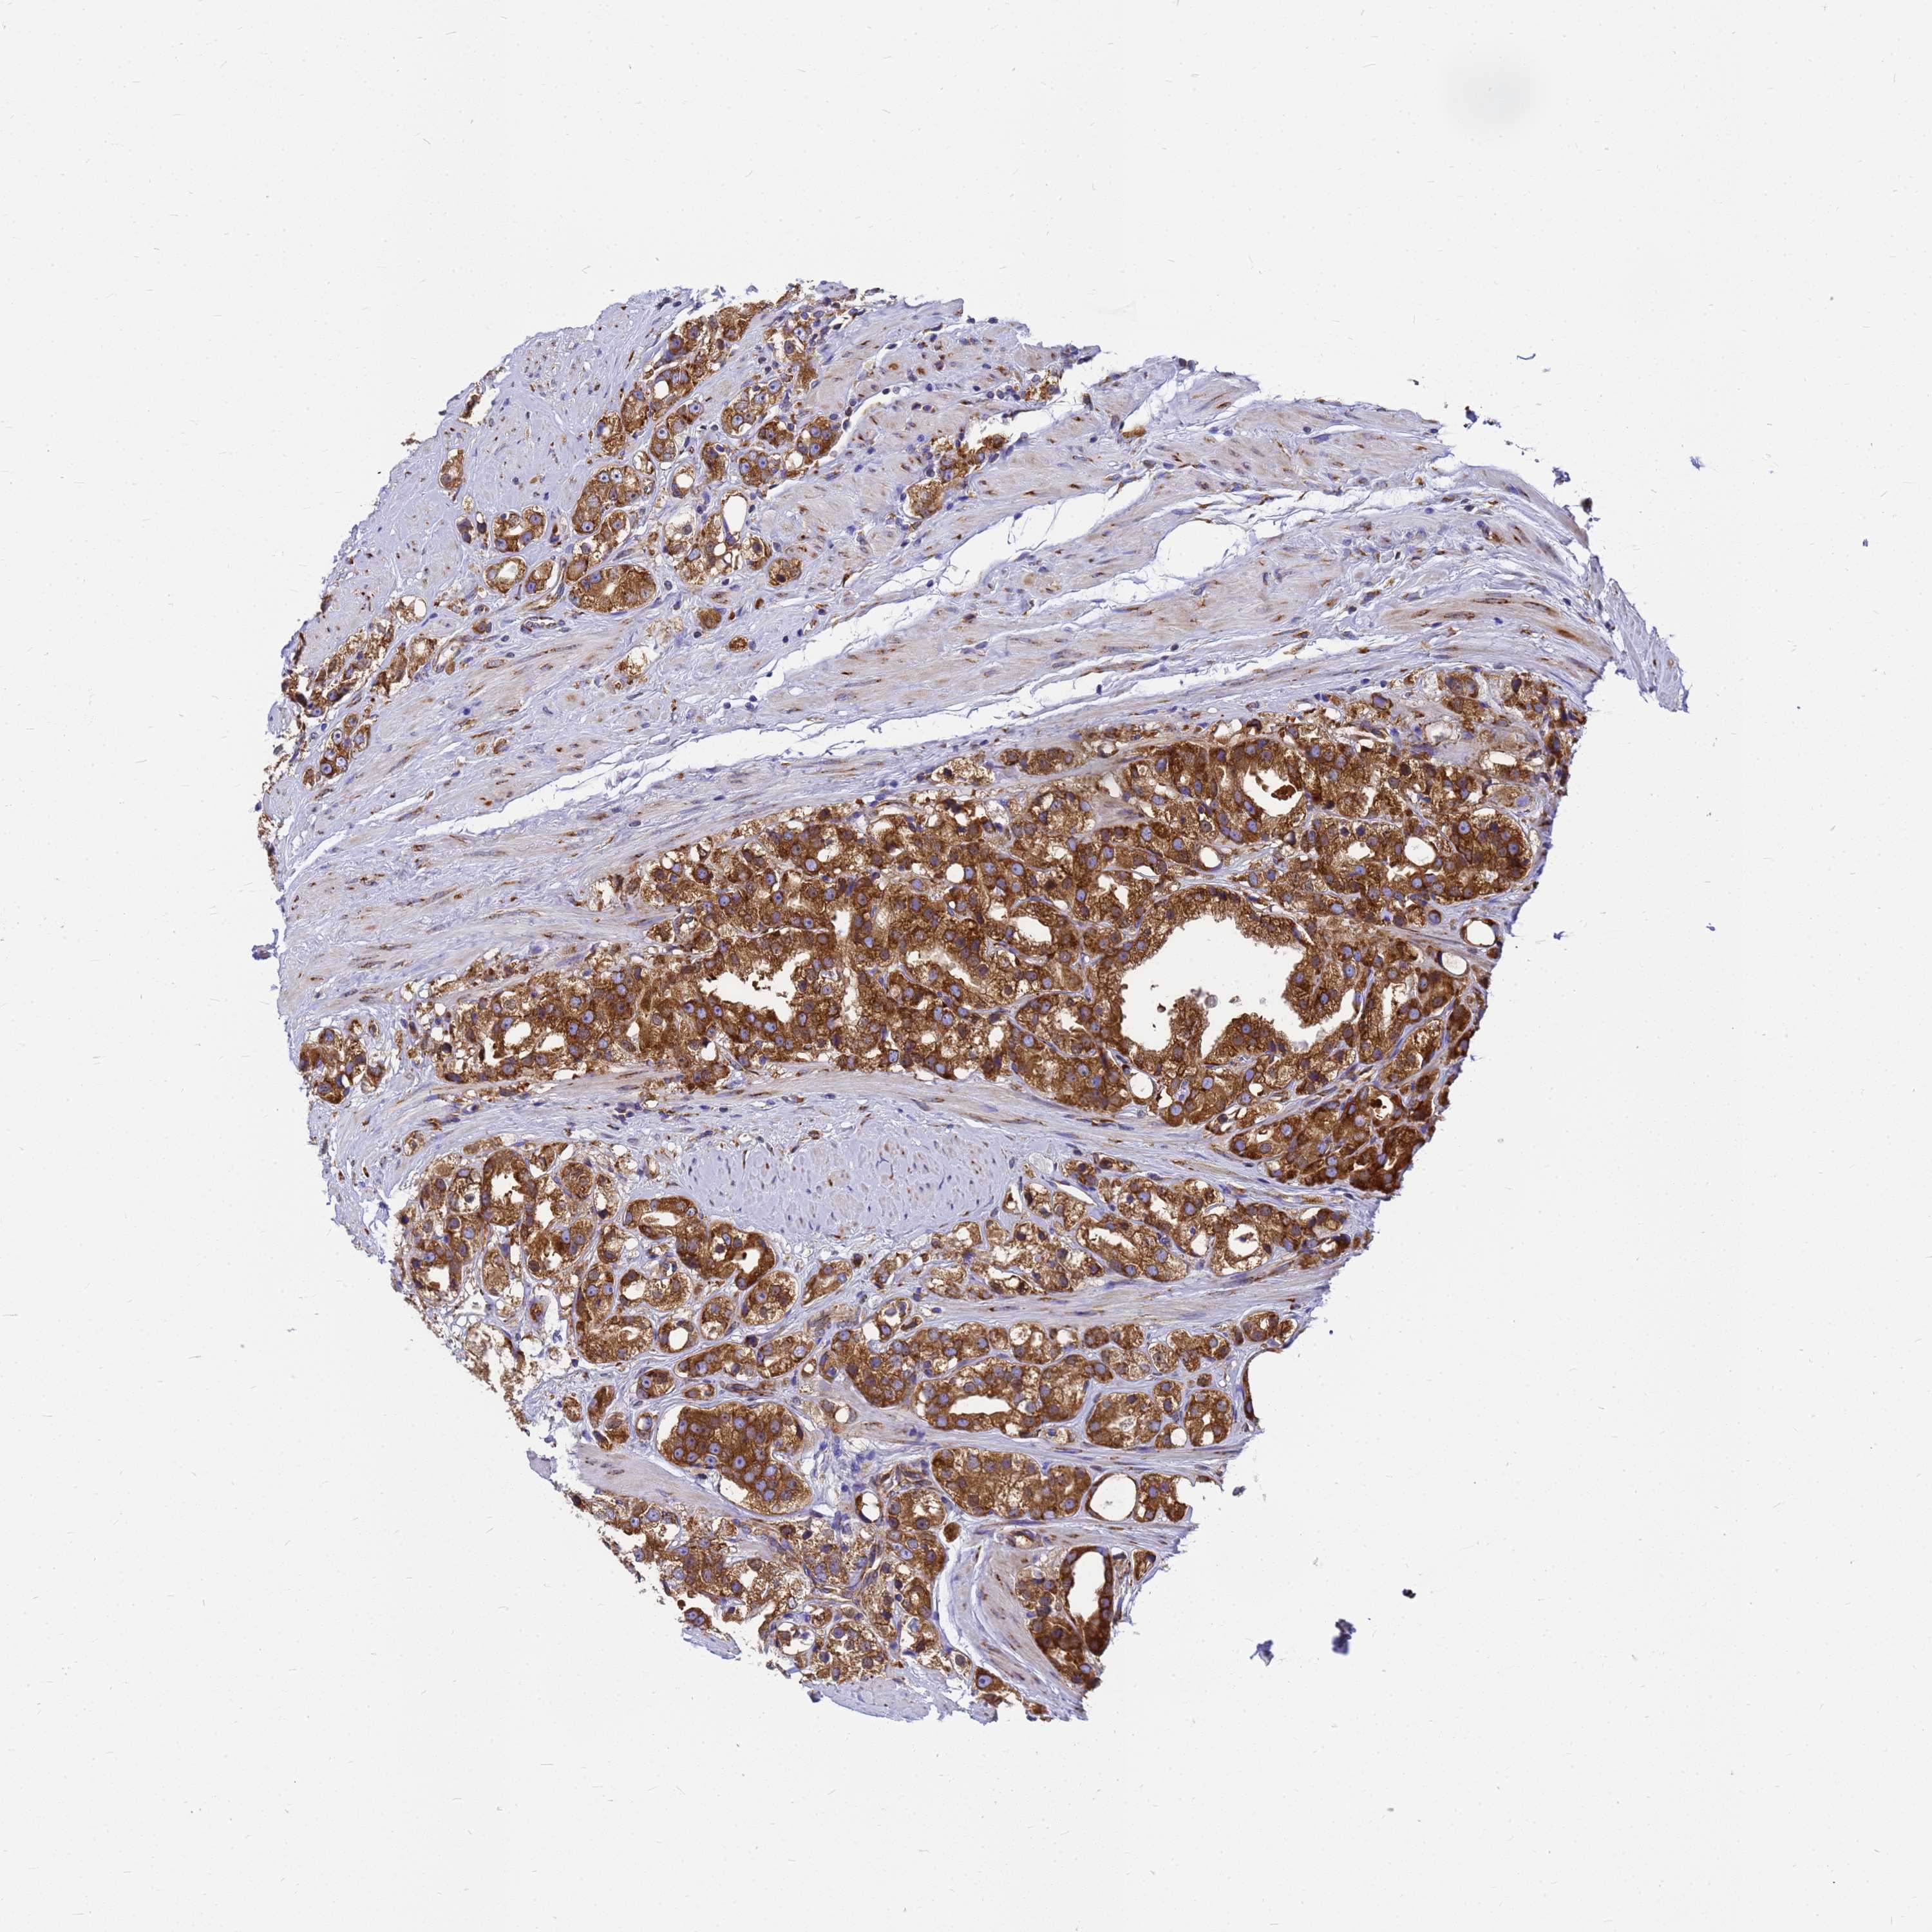

PROSTATE CANCER - Protein expressioni

A mouse-over function shows sample information and annotation data. Click on an image to view it in a full screen mode. Samples can be filtered based on level of antibody staining by selecting one or several of the following categories: high, medium, low and not detected. The assay and annotation is described here.

Note that samples used for immunohistochemistry by the Human Protein Atlas do not correspond to samples in the TCGA dataset.

Antibody stainingi

Antibody staining in the annotated cell types in the current human tissue is reported as not detected, low, medium, or high, based on conventional immunohistochemistry profiling in selected tissues. This score is based on the combination of the staining intensity and fraction of stained cells.

Each image is clickable and will lead to virtual microscopy that enables deeper exploration of all samples and also displays staining intensity scores, fraction scores and subcellular localization as well as patient and tissue information for each sample.

Antibody HPA045101

Staining

High

Medium

Low

Not detected

Intensity

Strong

Moderate

Weak

Negative

Quantity

>75%

75%-25%

<25%

None

Location

Nuclear

Cytoplasmic/membranous

Cytoplasmic/membranous,nuclear

Adenocarcinoma, NOS

Adenocarcinoma, High grade

Adenocarcinoma, Low grade